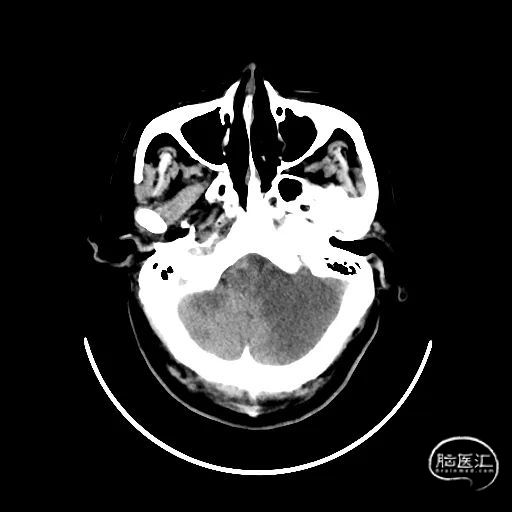

颅脑CT:未见明显缺血/出血病灶。

CTA提示:右侧椎动脉纤细,左侧椎动脉V1、V4段纤细。

MRI提示小脑缺血性改变。